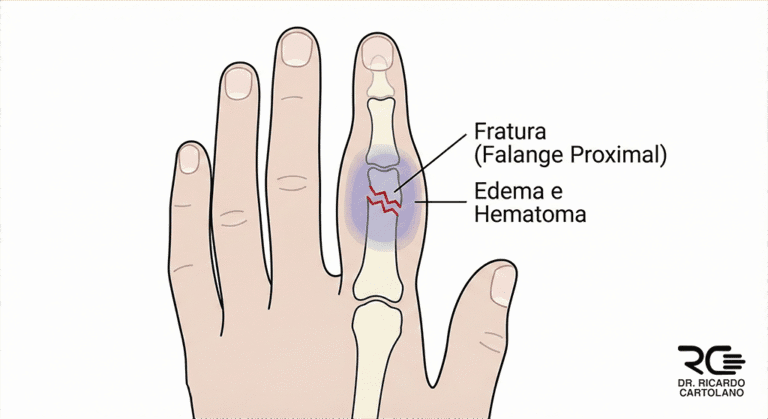

As falanges são os pequenos ossos que formam o esqueleto dos nossos dedos. Cada um dos seus dedos (do indicador ao mínimo) possui três falanges: a proximal, a média e a distal (ponta do dedo). O polegar é a exceção, possuindo apenas duas falanges.

Uma fratura de falange é simplesmente a “quebra” ou “trinca” de um desses ossos. Elas podem ser lesões simples e estáveis ou graves e complexas, dependendo de como o osso se quebrou.

Os sinais de um dedo quebrado são geralmente óbvios e aparecem imediatamente após o trauma:

Dor: Intensa e imediata no local da pancada.

Inchaço: O dedo incha rapidamente.

Hematoma: O local fica roxo ou azulado devido ao sangramento sob a pele.

Deformidade: Este é um sinal claro. O dedo pode parecer “torto”, “curto” ou “encavalado”.